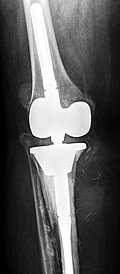

Kurze Vorgeschichte: Herr S, ein 67-jähriger Patient, erhielt 2011 (Abbildung 1) bei ausgeprägter Gonarthrose eine primäre KTEP rechtsseitig. Im weiteren Verlauf zog er sich 2017 eine periprothetische Tibiafraktur zu, die mit einem Knieendoprothesenwechsel auf ein achsgeführtes Implantat (Abbildung 2) und Schaftverlängerung der Tibia im September 2017 ex domo therapiert wurde. Im Verlauf zeigten sich eine anhaltende Sekretion und eine partielle Nekrose am unteren Wundpol.

Eine Röntgendiagnostik des rechten Kniegelenkes in 2 Ebenen wurde eingeleitet. Hierbei zeigte sich eine stabil einsitzende Revisionsprothese ohne aktuelle Lockerungszeichen.